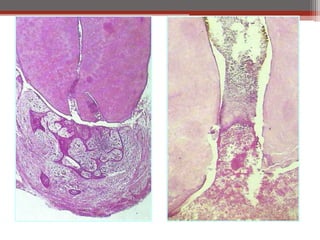

Histopathological Features:

• The polyp consists of granulation tissue.

• It contains delicate connective tissue, fibers and blood vessels.

• Mononuclear inflammatory cell infiltration.

• The polyp is covered with SS epithelium.

Chronic Hyperplastic Pulpitis Etiology: ClinicalFeatures: • Opened cavity. • Red pinkish soft nodule protruding • Starts as chronic or into the cavity. acute. • Almost in children and young adults. • Wide apical foramen • Relatively insensitive to manipulation. [Children]. • Most common in deciduous molars. • Must be differentiate from gingival polyp. Histopathological Features: • The polyp consists of granulation tissue. • It contains delicate connective tissue, fibers and blood vessels. • Mononuclear inflammatory cell infiltration. • The polyp is covered with SS epithelium. • Treatment: RCT or extraction of the tooth.